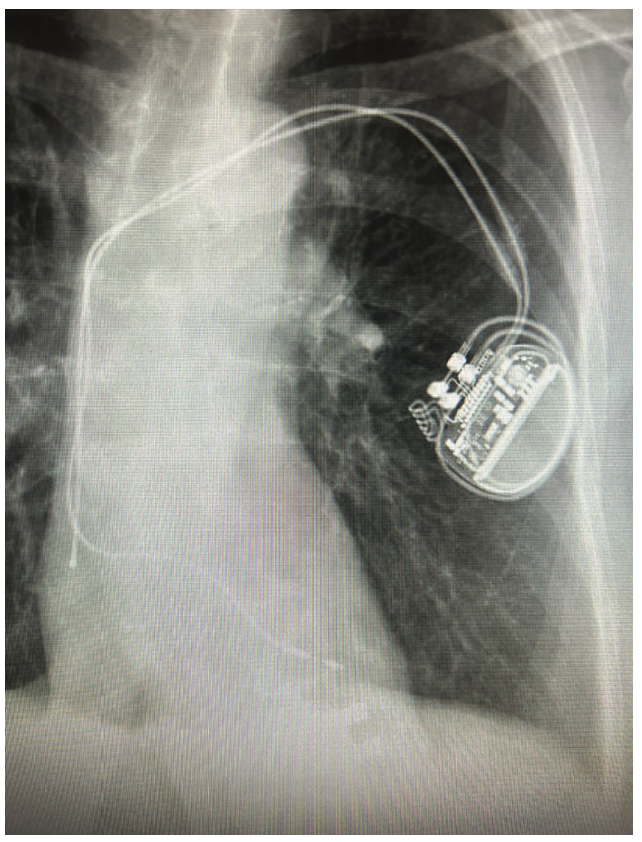

The patient is a 60-year-old female with sick sinus syndrome and a permanent dual-chamber pacemaker (Ingevity MRI pacing lead (model/length 7741/52 cm and 7740/46 cm, Boston Scientific) implanted 5 years prior. She was admitted for heart failure (HF) with an ejection fraction (EF) of 40%, atrial fibrillation (AF), and moderate mitral regurgitation (MR). The chest x-ray showed the ventricular lead to be in the left ventricle (LV) via the atrial septum (Figures 1 and 2). She was referred to us for extraction and device revision. The case raised several questions as to management of HF, AF, and an abnormally located lead impinging upon the mitral apparatus. Surgical extraction of the lead was discussed as well. As the onset of HF coincided with AF, and considering that the patient could require atrial septal device (ASD) closure after extraction, it was recommended that the patient first undergo AF ablation before extraction. She underwent pulmonary vein isolation and additional LA posterior wall and cavotricuspid isthmus ablation at our institution. Intraprocedural transesophageal echocardiography (TEE) allowed us to confirm the aberrant course of the lead and impingement on the mitral apparatus. Keeping in mind the relative urgency due to MR, she was scheduled for extraction 3 weeks later. Apixaban was held on the morning of the procedure and resumed post procedure the same evening. The case was coordinated with the interventionalist, cardiothoracic (CT) surgeon, and neurointerventional radiologist, anticipating potential issues such as development of a large ASD post extraction that could require a closure device, mitral apparatus damage resulting in acute MR and decompensation, and cerebral embolization of debris. In addition to the usual femoral sheaths (discussed later), the Sentinel Cerebral Protection System (Boston Scientific) was positioned prophylactically via the right radial approach by the interventionalist in the hybrid room (Figure 3). TEE imaging did not reveal any thrombus or vegetations on the lead body. A 12 French (F) GlideLight Laser Sheath (Philips) was used along with a VisiSheath Dilator Sheath (Philips). Laser applications were performed along the lead, specifically in the innominate vein and to cross the atrial septum. The VisiSheath was used to break adhesions along the mitral annulus and LV apex. A larger (14F) sheath may have theoretically allowed less shearing of debris and embolization risk, with the potential downside of creating a larger ASD. In a more chronically implanted lead, this issue may be taken into consideration when selecting sheath size. The lead came out with countertraction at the LV apex. A residual patent foramen ovale was seen that was small and did not require closure. MR was negligible with no visible damage to the mitral valve leaflets or chordal apparatus. The new right ventricular (RV) lead was implanted on the RV septum, confirming position by orthogonal fluoroscopic views and TEE. The patient had intact conduction with a narrow QRS and the decision was made not to implant a conduction system pacing lead; instead, the RV lead was positioned on the RV septum. No debris was seen in the Sentinel device after removal and careful examination. She was discharged home the next day with an uneventful postop course. She remains symptom free without further AF or HF after 6 months and has a normalized LVEF.